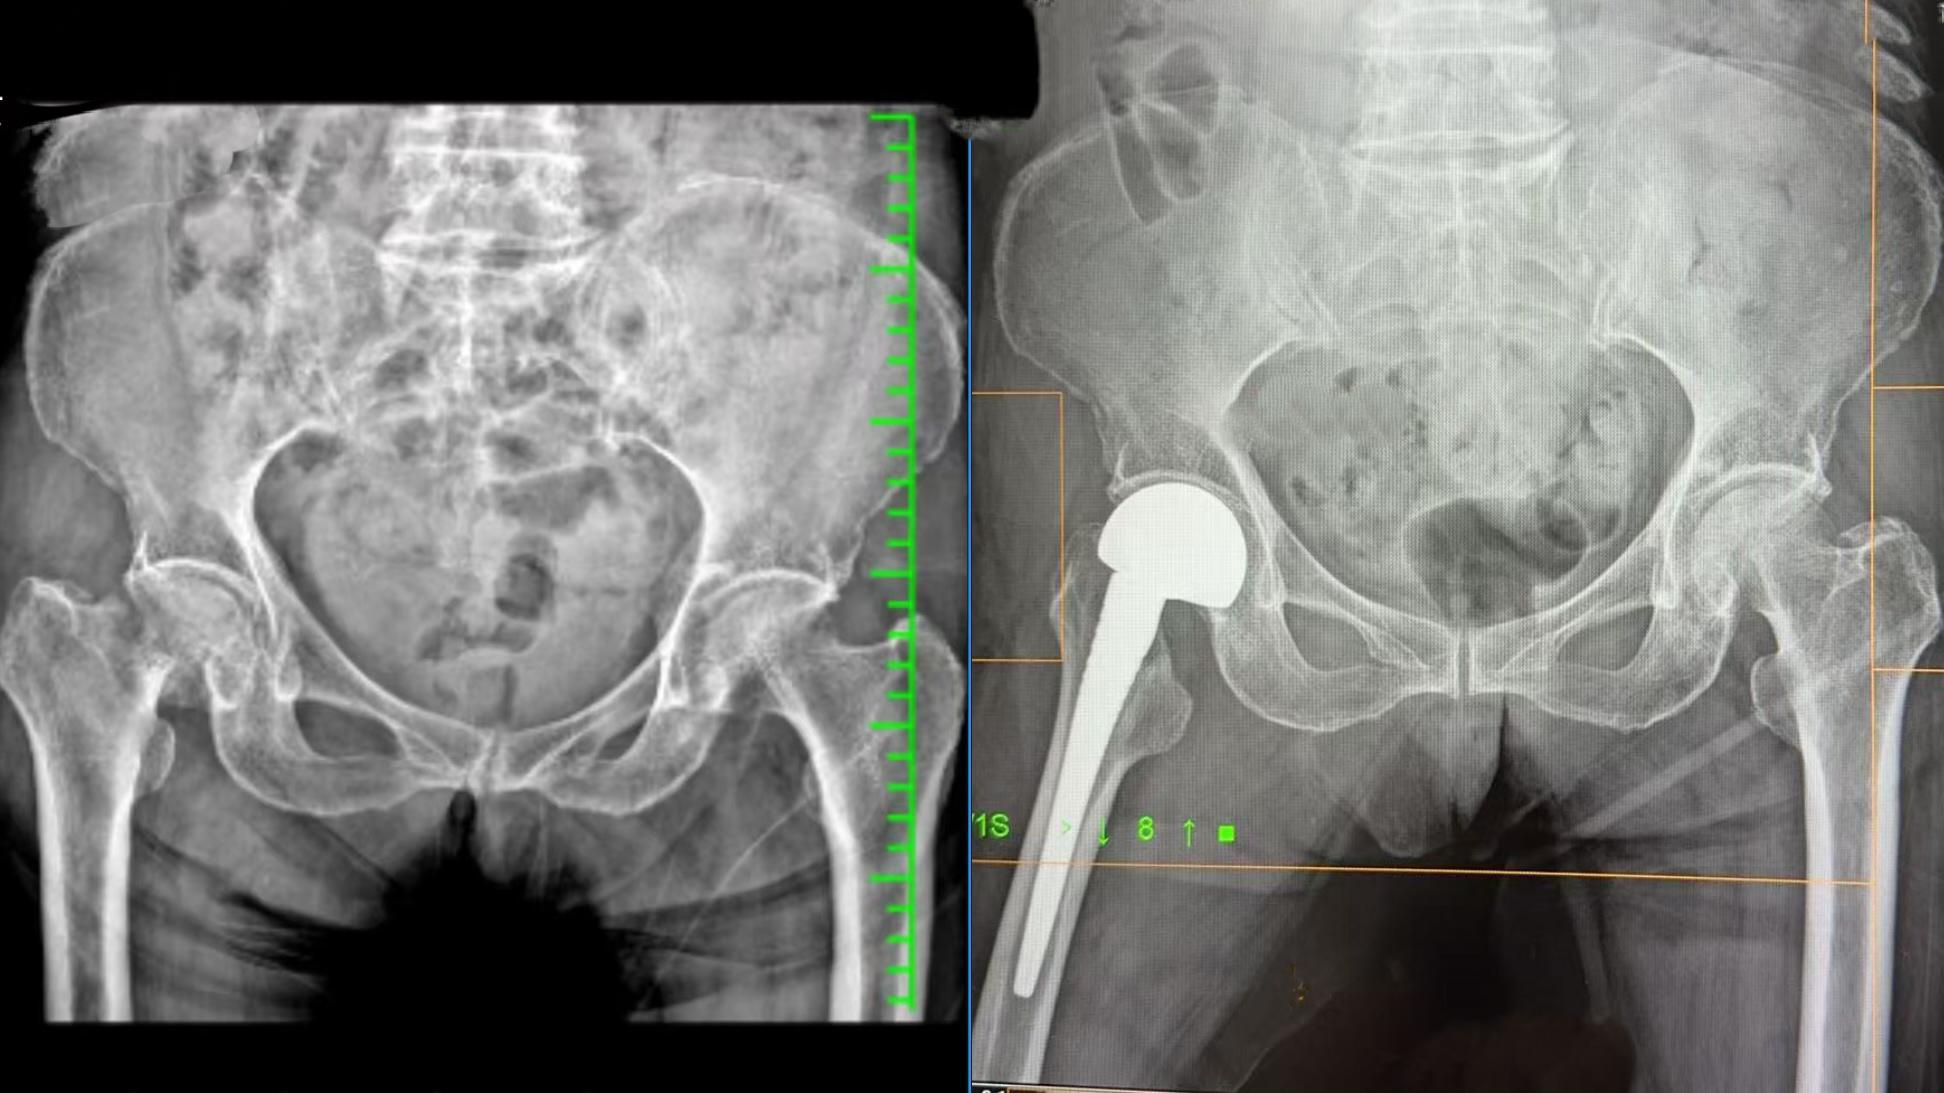

在南医三院关节外科主任方航的统筹协调下,团队第一时间对患者进行全面评估,并迅速制定了个体化的手术方案。考虑到患者高龄、基础病复杂以及迫切希望回家过年的愿望,团队争分夺秒完善术前检查,精确评估心肺功能与手术风险,确保万无一失。

2月15日,副院长张荣凯主刀,带领邹玉明、吴桂勤等人,在麻醉科团队的精准护航下,多学科团队紧密协作,手术顺利完成。